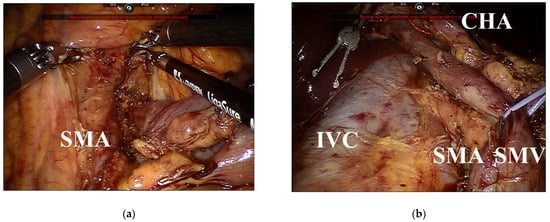

2.1. Surgical Approaches to the SMA in RPD

2.2. Dissection around the SMA Using the Right Approach

2.3. Dissection around the SMA Using a Combination of the Left and Right Approaches